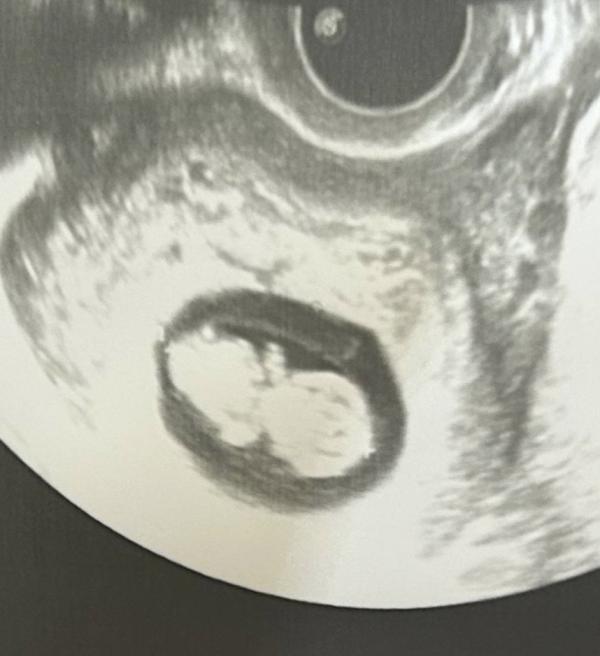

3 сантиметра человека

9,5 недель по узи (9,6 по месячным)

Поразительно, что через 2 недели там будет не черепашка, а полноценный человек 😍

Это так невероятно 😍 у меня такой же срок, вчера делала узи. А он ьам крутился и вертелся, махал ногами и руками 🙈 на как это возможно в трех сантиметрах😄